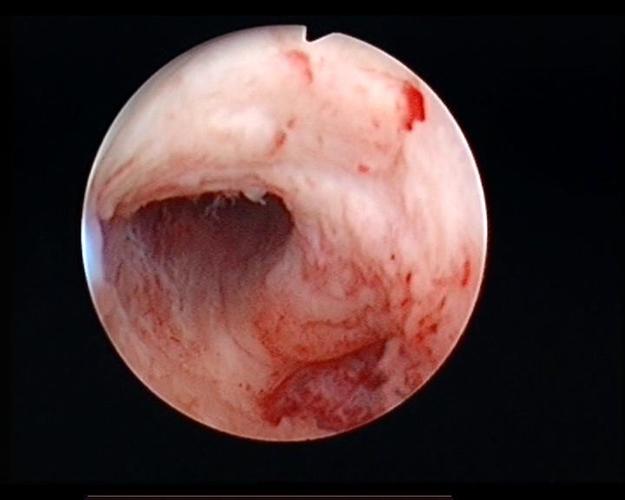

宫腔粘连图片宫腔镜

宫腔粘连图片宫腔镜,宫腔粘连严重图片

宫腔粘连

重度宫腔粘连图片

宫腔粘连宫腔镜